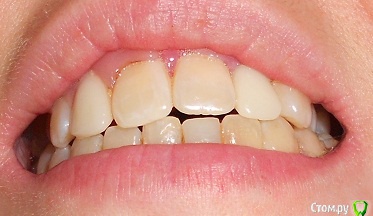

Добрый день, прошу проконсультировать, как поступить в моей ситуации.Прикус как могла сфоткала, сейчас проблема в отсутствии 2х верхних резцов, на их место поставила импланты-но они не прижились-в качестве наиболее вероятной причины выдвигают-недостаточность места, близость к корням соседних зубов.Возможно ли в моем случае ситуацию исправить брекетами.Прикус по-моему неправильный, ВЧ узкая, перекрытие НЧ есть в р-не передних зубов и задних, в середине картина не очень.Возможно ли немного расширить ВЧ. И беспокоит не будут ли смещаться зубы на место отсутствующих?Сейчас на месте одной из двоек съемная бабочка на месте другой имплант который нужно удалять.

Вы правильно обрисовали картину. У вас дефицит места для  "двоек" ,  также перекрестный прикус слева  (справа Вы не показали) (обратное перекрытие зубов, что чревато для сустава.) Также отсутствие верхнего бокового зуба ("пятерка"),  также ретенированные восьмерки (их надо удалять), ну и качество пролеченных зубов оставляет желать лучшего.

Если хотите  все сделать не только эстетично, но и функционально, то потребуется поставить брекеты и создать место под недостающие зубы.